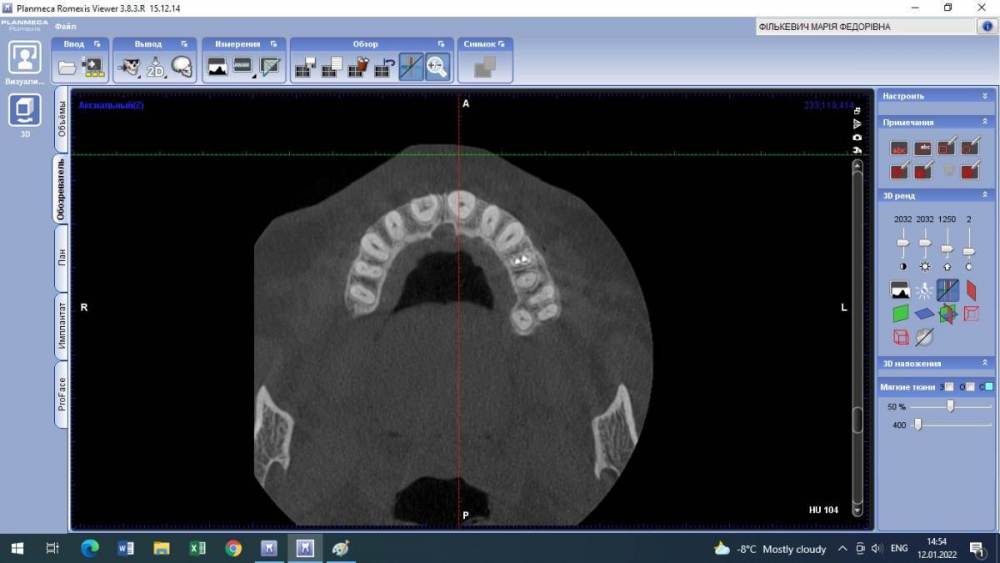

Lyubanya Опубликовано 12 января, 2022 Поделиться Опубликовано 12 января, 2022 Здравствуйте, коллеги. Вот такой случай. 11 зуб, пациентка 1963 г.р. Найдено случайно на КТ, делала его 3.09.21 по другому поводу, я взяла посмотреть для эндо премоляров. Визуально во рту вижу легкую розоватость пришеечно, и есть место, где цепляет зонд. Вопросов много. Каков точный диагноз? И что делать с этим зубом? Есть ли у него шансы пожить еще? Я так понимаю по возможности делается эндо в таком зубе. Если есть шансы то какова тактика? Ссылка на комментарий

Lyubanya Опубликовано 15 января, 2022 Автор Поделиться Опубликовано 15 января, 2022 9 часов назад, Александр23712 сказал: @Lyubanya Лично я бы, если не беспокоит, пока не трогал, но пациентку бы предупредил и кт показал. Может она ничего и не поймет, зато, когда/если заболит, придет к вам. Процесс прямо чуть ниже шейки. Как я понимаю, чтобы такое лечить, вам надо сначала лоскут откинуть, дальше в зависимости от кортикальной пластинки. Но у композита к дентину спорная адгезия ? . По поводу эндо не представляю, зачем депульпировать зуб раньше срока. Сделайте прицельный еще в 2 проекциях, интересно посмотреть Какая конкретно это резорбция? Разряжение вокруг основного канала = внутренняя резорбция корня? Или нет? Просто пыталась найти инфо, и нашла что внутренние это эндо. Но если можно наблюдать, то я только за) Пациентка работает у нас санитарочкой и я совсем не хочу ей лишнего стресса и тем более потери зуба. Хотела с главврачом обсудить, но пожалуй пока не буду. У меня на КТ нашлось новообразование, он ходил давил что надо удалить зуб вместе с ним. В итоге спустя полгода оказалось, что это цементно-костная дисплазия и ничего удалять не нужно. Спасибо Рогацкину.? И как мне сделать две проекции на пленочном?? 9 часов назад, Дмитрий Л. сказал: Реставрация без эндо; риск рецессии. Имеете ввиду перекрыть то место, где зонд цепляется? Ссылка на комментарий

Дмитрий Л. Опубликовано 15 января, 2022 Поделиться Опубликовано 15 января, 2022 Это инвазивная цервикальная резорбция, связи с пульпой нету, хирургически можно откинуть лоскут и реставрировать. Риск рецессии. Другое лечение - выжидание, риски прогресса с потерей зуба, смотрите на возраст пациента. 1 Ссылка на комментарий

Lyubanya Опубликовано 16 января, 2022 Автор Поделиться Опубликовано 16 января, 2022 8 часов назад, Дмитрий Л. сказал: Это инвазивная цервикальная резорбция, связи с пульпой нету, хирургически можно откинуть лоскут и реставрировать. Риск рецессии. Другое лечение - выжидание, риски прогресса с потерей зуба, смотрите на возраст пациента. А вот размытость дентина вокруг хода канала, это она же? Думала насчет лоскута, но я так понимаю поможет он не особо, там альвеола уже.? Ссылка на комментарий